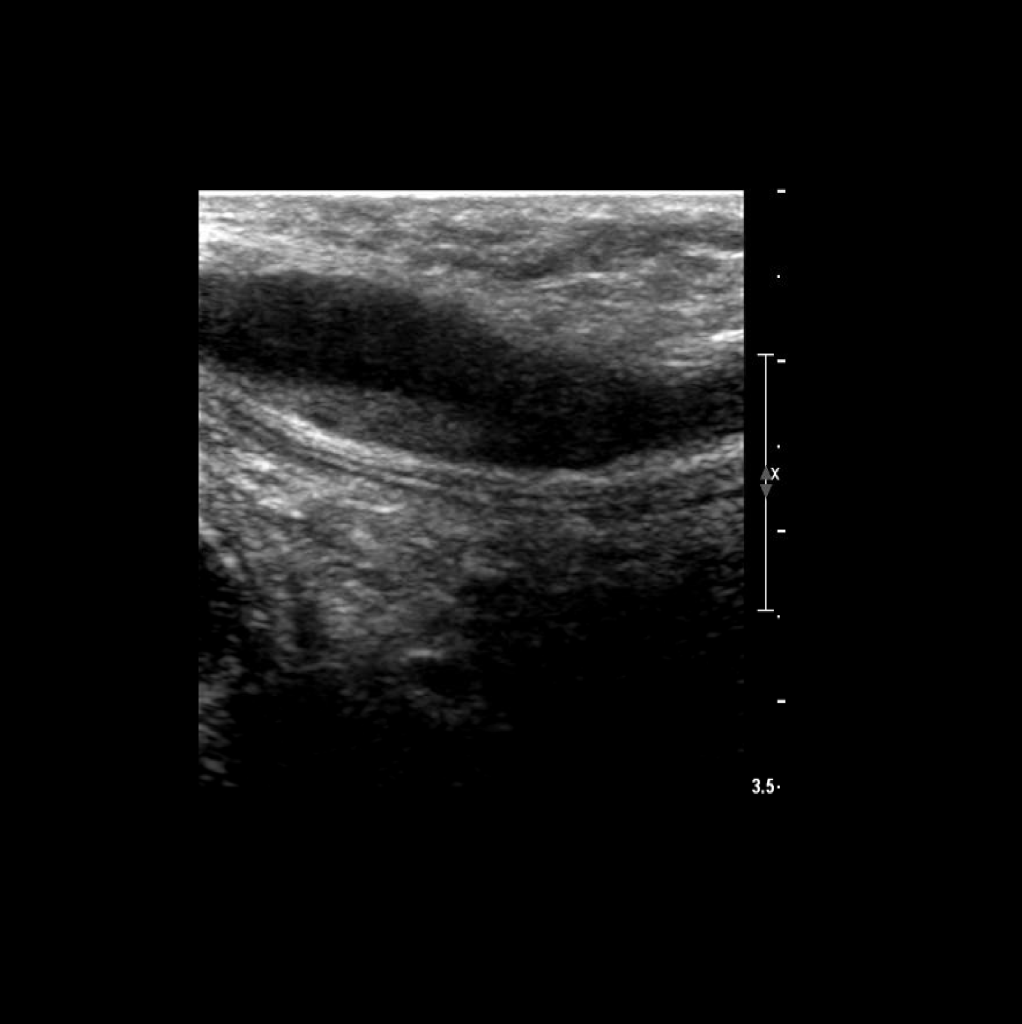

Scan the basilic vein in grey scale, compression, color doppler and spectral doppler

Thrombus of the right basilic vein